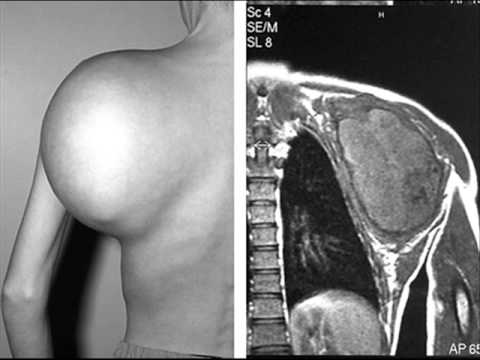

Rare Cancers, Sarcoma

Ewing Sarcoma